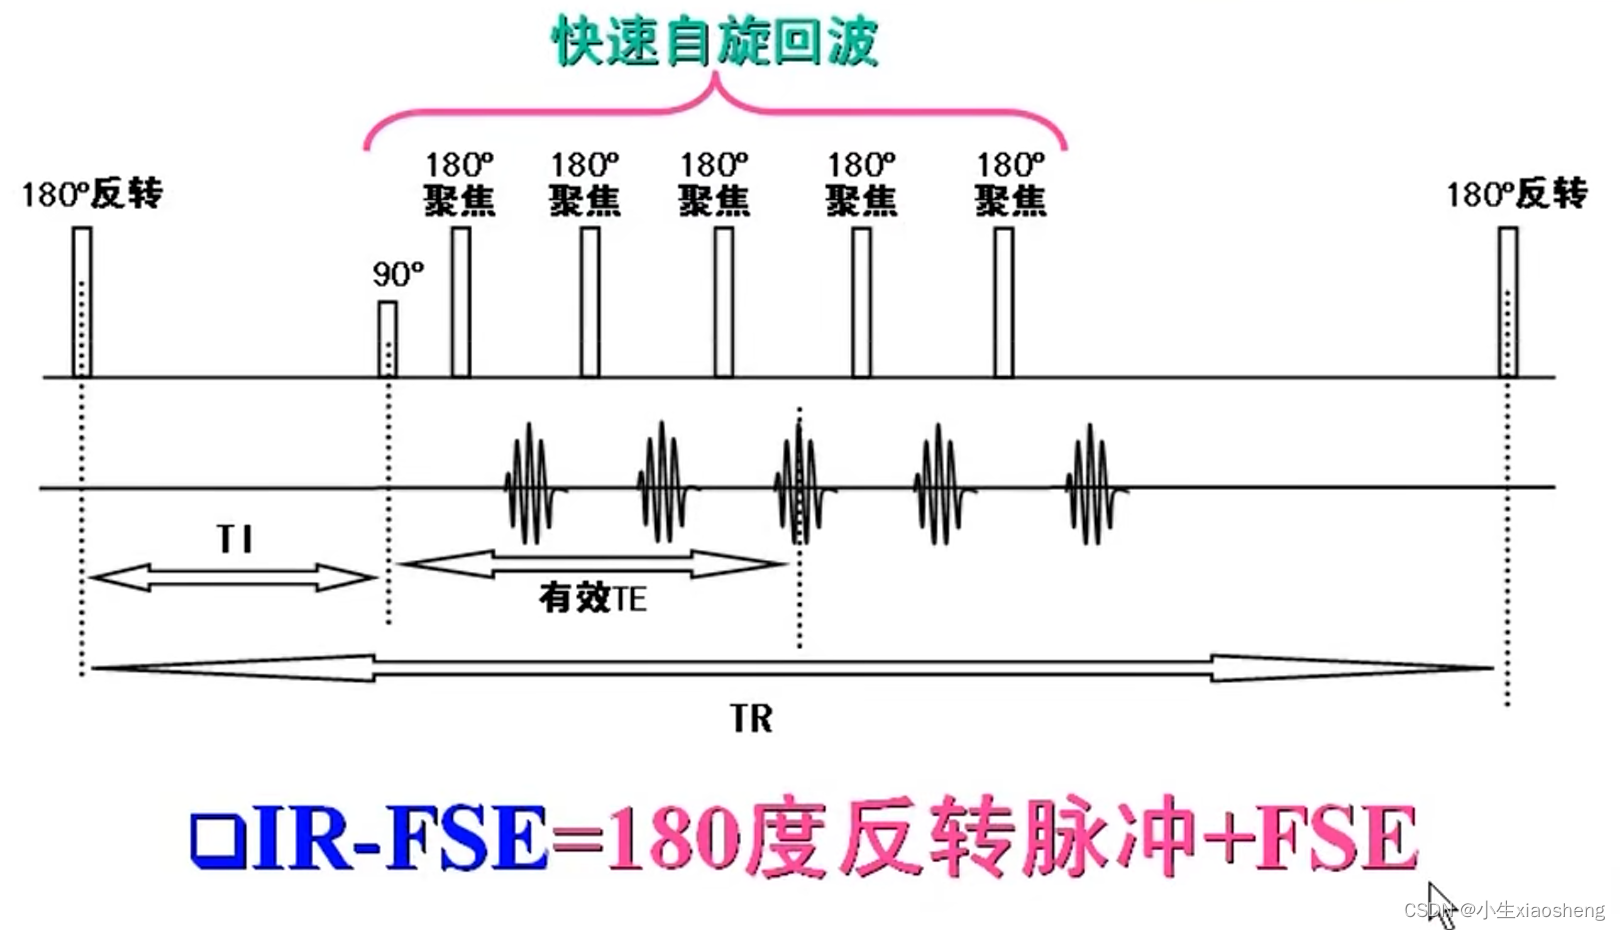

自旋回波--90度和180度填充K空间;反转恢复--在自旋的基础上两边加180度;梯度回波--消除每次脉冲留下的影响,以及波的次数;propeller==》K空间填充技术和FSE或FIR结合用于减少运行伪影;EPI==》采集方式,一次激发采集多个回波的形式但与单次不一样;PRESTO和GRASE==》前面几种的一种结合形成新的。

因为这里有很多的180度,所以一次能填充很多K空间线。两个90度之间的时间还是叫做TR,180度的个数叫做ETL,90度到中间个数的180度叫做有效TE,两个180度之间的叫做ES。

四、反转恢复类序列

2.快速反转恢复序列

螺旋桨和刀锋序列,其实也就是常规FSE(快速自旋)或IR-FSE(反转恢复)序列的K空间填充,可以和其他技术结合来减少运动伪影。